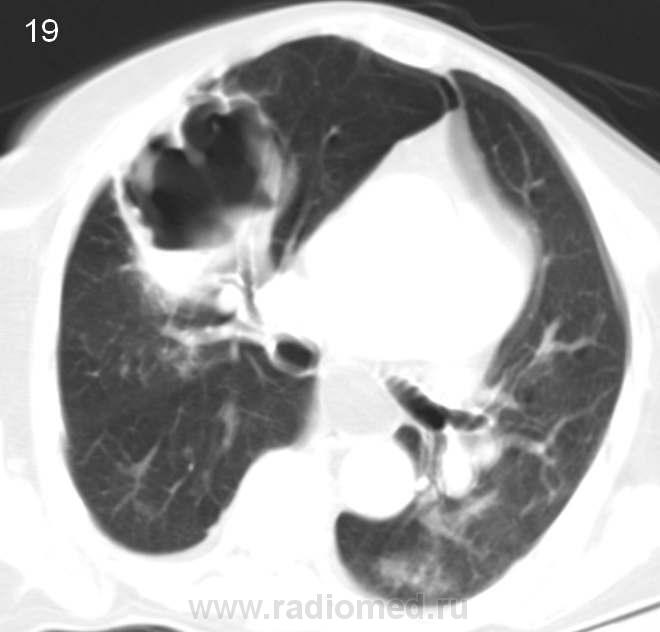

Больная 80 лет. Госпитализирована в терапевтическое отделение. Состояние тяжелое.Флюорографию не проходила много лет. Прошу высказать Ваше мнение о данной патологии. Это не игра. Диагностика заболевания. Жду. С уважением, Nikolas

Полость большая, стенки неровные, толщина различная, есть что-то вроде секвестра, но думаю- солидный компонент. На первое место выставил бы полостную форму рака, а остальное в виде вторичного наслоения. За ТЭЛА не думаю, была бы клиника, да и распад слишком большой.

Кровь и мокрота: что в анализах? Температура? Состояние тяжелое, а какова клиника, анамнез заболевания - остро, хронически? Есть ли динамика снимков? Есть ли связь с органами брюшной полости? Одни вопросы sad. Ни верхушек, ни низушек, полной картины не складывается, и без мягкотканного окна только гадать остается. Будь у меня такое исследование без ничего, написала бы полостное образование (диф.ряд от толстой кишки в грудной полости до абсцесса легкого).

1)синдром кольцевидных теней  ,неправильной формы с толстыми стенками ,наличием в некоторых горизонтального уровня ,2)уплотнения по типу матового стекла(вероятнее всего кровоизлияния) ,3)синдром круглой тени(вероятнее всего гранулема),4)синдром очаговых теней ,5)локальное субплевральное уплотнение по типу консолидации,6)мелкие сгруппированные ацинарные тени,7)субплевральные линейные тени(фиброз),8)единичный крупный л.у. параэзофагеальной группы со сниженной дкнситометрической плотностью,9)крупная параэзофагеальная грыжа,10)левая доля печени со сниженной денситометрической плотностью?(есть сомнения ввиду лишь нативного исследования ).исключить гранулематозы(туберкулез и вегенер) и грибковое поражение

Справа вокруг полости до противного чисто... ну немного паренхима поджата, что неудивительно. Полость крупная, с перегородками, с некротическими массами и жидкостью, стенки неравномерно толстые. На первом месте выставила бы полостную форму рака (либо солитарный гигантский мтс с распадом), на второе - туб.каверну (нет отсева или я не вижу, что как-то мало подходит под тбс), на третье - гигантский абсцесс (такая ареактивность, что лимфоузлы не отреагировали?...). Возможность грибов мне кажется достаточно маловероятной. Вегенера и последствия инфаркта при ТЭЛА тоже возможно, но такая крупная полость в 80 лет мне кажется для этих вариантов также маловероятной. Могу ошибаться.

- сегментарная локализация: посмотрите - деструкция занимает четко ограниченную анатомическую зону, широко прилежит к плевре (субплеврально)

- форма: клиновидная

- контуры: неровные, как бы "полицикличные" контуры деструктивной полости - очень характерный признак для больших инфарктов. Туберкулезные полости обычно имеют более правильные контуры (если конечно они не совсем старые, но при этом вокрг должен быть явно выраженный фиброзный процесс - тут этого нету)

- стенка - не толстая! При опухолях маловероятно что была бы такой толщины стенка. Причем она относительно равномерная. (на нижний отдел не смотрите - там секвестр остался от легкого а не стенка).

- характер секвестра - ячеистого характера (довольно типично выглядит). Правда и не при ТЭЛЕ выглядит подобно, но все же..

Ну и самое оснвое: в  окружающем легком явных изменений, ожидающихся при других патологических процессах не выявлено: например при такой деструкции при тбц ожидались бы очаги или выраженый фиброз, при опухоли с такой деструцкции тоже ожидали очаги, лимфоузлы, обструкцию бронхов (а они спокойно проходят в дестрктивной полости), изменения в легочной архитектонике и тд.